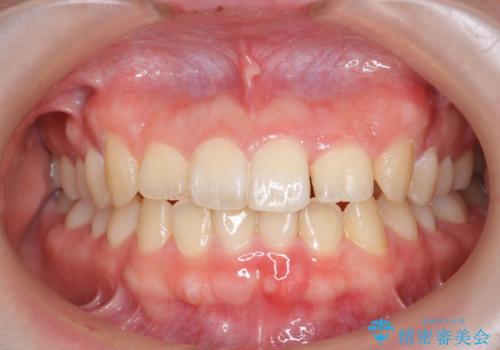

前歯のねじれを治したい (部分矯正を併用したマウスピース矯正)

- ねじれの目立つ前歯を改善したいと、矯正治療を希望され来院されました。

インビザラインの不得意な上顎前歯のねじれの改善を、マウスピース矯正を行う前に前歯のみの部分ワイヤー矯正を行うことで治療期間の短期化を目指します。

上顎前歯のねじれはマウスピースで治りづらいため、マウスピース矯正の治療期間の長期化をきたしやすい歯列不正です。

マススピース矯正を始める前に、部分ワイヤー矯正を行うことで治療の短期間化・良好な仕上がりを達成することができました。